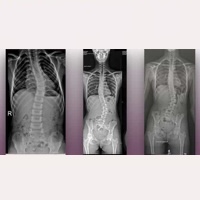

脊柱側弯症

特発性脊柱側弯症